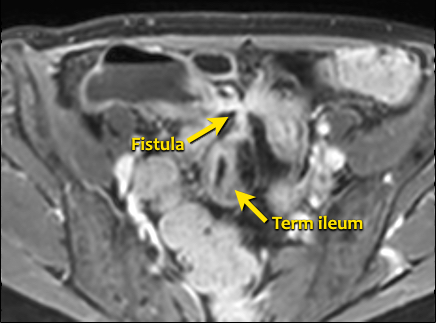

Rò

Đường xoang và đường rò là các biến chứng thường gặp ở bệnh nhân mắc bệnh Crohn.

Cả hai đều ngấm thuốc rõ rệt trên chuỗi xung T1W sau tiêm gadolinium.

Đường rò có thể biểu hiện dưới dạng cấu trúc phân lớp kiểu ‘đường ray tàu hỏa’ hoặc như một cấu trúc tuyến tính ngấm thuốc.

Đường rò có thể đi từ quai ruột này sang quai ruột khác, đến một tạng rỗng khác hoặc ra da.